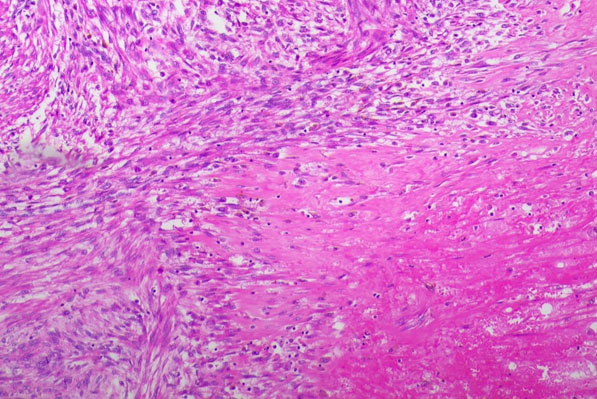

The initial post-operative histology confirmed endometriosis and initially reported STUMP, therefore a second opinion was sought. This further expert’s impression was that the equivocal necrosis was very likely degenerative in nature given the characteristic ischemic type effect and the relative paucity of atypia and mitotic activity, as seen Figure 1.

Figure 1: Ischemic type necrosis and relative paucity of atypia and mitotic activity.